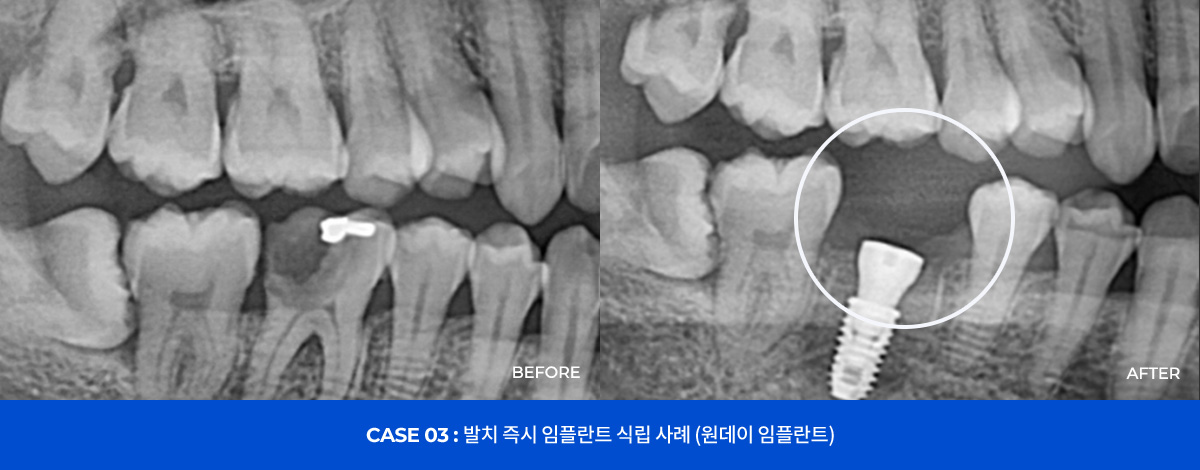

| 임플란트 | 임플란트 | 오스템SOI(구치) | 140 |